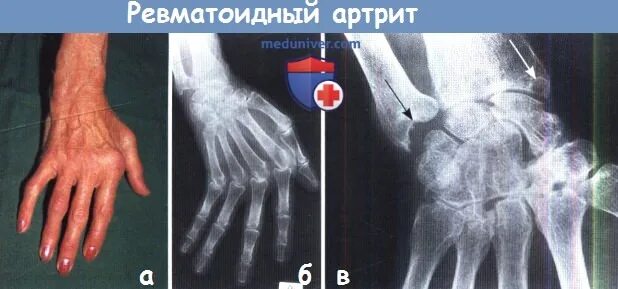

Ульнарная девиация кисти ревматоидный артрит. ревматоидный артрит ульнарная девиация пальцев кистей. кисти с ревматоидным артритом бутоньерка. лорнетка ревматоидный артрит.

Ульнарная девиация кисти ревматоидный артрит. ульнарная девиация кисти рентген. типы деформации кисти при ревматоидном артрите.

Рентгенологические стадии ревматоидного артрита. паукообразная кисть ревматоидный артрит. ревматоидный артрит кисти рентген. ревматоидный артрит пястно фаланговый сустав.

Ревматоидный артрит кисти рентген. ревматоидный артрит деформация кисти. полиартрит рентген кистей. ульнарная девиация кисти рентген.